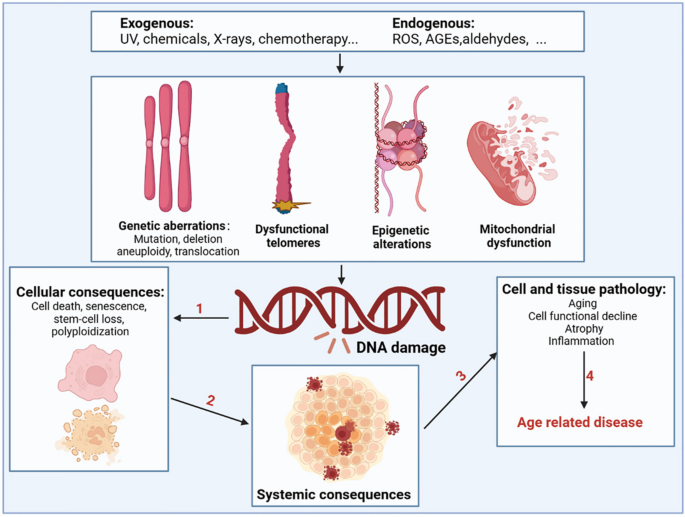

Relationship between DNA damage and aging

During aging, numerous exogenous and endogenous genotoxins, photoaging, and mechanical stress in tissues continuously induce DNA damage (Fig. 2 ). Approximately 10 5 DNA damage events occur in mammalian cells every day, although most of the DNA damage is effectively excised or repaired. Notably, a small portion escapes the DNA damage detection and repair system, subsequently resulting in failure to repair or repair errors [ 48 ]. Many studies using mammalian models have confirmed an inextricable link between DNA damage and aging [ 49 , 50 , 51 , 52 ]. As aging progresses, the DNA repair capacity gradually declines, and the increased molecular phenotype of genomic instability becomes the main marker of aging. Markers of DNA damage are found in patients with age-related diseases such as cardiovascular disease [ 53 ], Alzheimer’s disease [ 54 ], and cancer [ 55 ], suggesting that DNA damage is directly related to the incidence of these diseases. Patients with genetic or acquired defects in DNA repair proteins also exhibit features of premature aging and that differences in the location of the defect in the DNA repair system can lead to premature aging in different organs [ 56 ]. Specifically, RecQ helicase plays an important role in DNA recombination, replication, repair, and telomere maintenance, and its mutation may increase the incidence of Werner, Bloom, and Rothmund-Thomson syndromes [ 57 ]. Global genome nucleotide excision repair deficiency leads to a thousand-fold increase in skin cancer susceptibility and may accelerate neurodegeneration [ 58 ]. Impaired transcription-coupled repair mechanisms can cause typical age-related pathologies, such as neurodegeneration, osteoporosis, and atherosclerosis [ 59 ]. Hutchinson-Gilford progeria is associated with nuclear genome instability, defects in DNA double-strand break repair leading to telangiectasia and Nijmegen break syndrome, and defects in DNA cross-linking repair leading to anaemia [ 60 ]. In addition, DNA damage caused by mitochondrial defects is another underlying factor in a class of progressive diseases that affect multiple organs.

Drivers of DNA damage and the resulting systemic consequences. The nuclear and mitochondrial genomes are constantly exposed to exogenous substances (such as ultraviolet and X-rays, chemicals in food, water, and air), endogenous substances such as ROS, advanced glycation end products (AGEs), and aldehydes; this results in genetic abnormalities, including mutation, deletion, aneuploidy, translocation, dysfunctional telomeres, epigenetic alterations, and mitochondrial dysfunction. DNA damage and DNA damage response caused by the above factors can shock molecular processes and alter cell fate, such as cell death, senescence, and systemic breakdown of repair functions, eventually leading to the loss of cell and organ function and promoting the occurrence and development of age-related diseases